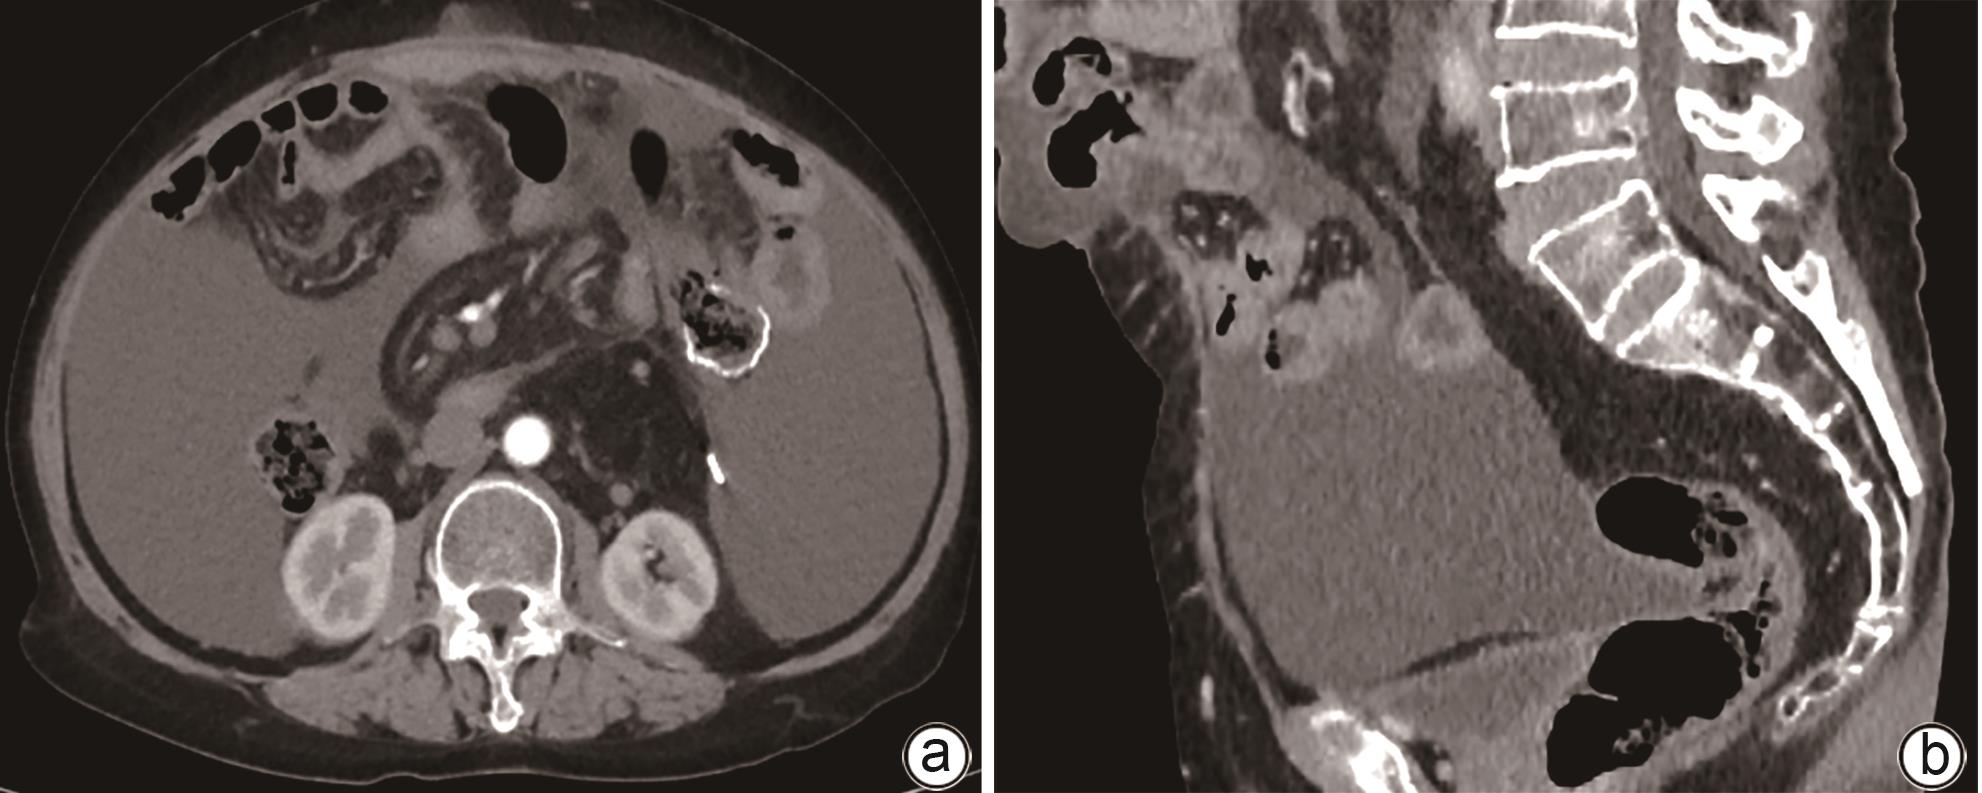

Value of preoperative alanine aminotransferase/aspartate aminotransferase combined with multi-phase CT radiological indicators in predicting clinically relevant pancreatic fistula after pancreaticoduodenectomy

Junhao PAN, Jian XIN, Chunhui WANG

2024, 40(9): 1859-1867. DOI: 10.12449/JCH240922

Abstract(880) HTML (364) PDF (2208KB)(55)

Abstract:

Objective  To investigate the risk factors for clinically relevant postoperative pancreatic fistula (CR-POPF) after pancreaticoduodenectomy (PD), and to establish a predictive model for early identification of CR-POPF.  Methods  A total of 244 patients who underwent PD in General Hospital of Northern Theater Command from January 2019 to October 2023 were collected, and based on strict inclusion and exclusion criteria, 179 patients were finally enrolled in this study. According to the presence or absence of CR-POPF, these patients were divided into non-CR-POPF group with 120 patients and CR-POPF group with 59 patients. Univariate and multivariate logistic regression analyses were used to determine the independent risk factors for CR-POPF, and a nomogram model was established based on such factors. The receiver operating characteristic (ROC) curve was used to assess the predictive performance of the model, the calibration curve was used to evaluate the calibration degree of the model, and the clinical decision curve and the clinical impact curve were used to analyze and validate the clinical application value of the model. The chi-square test or the Fisher’s exact test was used for comparison of categorical data between groups; the independent-samples t test was used for comparison of normally distributed continuous data between two groups, and the Mann-Whitney U test was used for comparison of continuous data with skewed distribution between two groups.  Results  Among the 179 patients, 59 (33.0%) developed CR-POPF. The multivariate Logistic regression analysis showed that alanine aminotransferase/aspartate aminotransferase (odds ratio [OR]=2.221, P=0.004), main pancreatic duct diameter (OR=0.276, P=0.022), the distance between the peritoneum and the anterior pancreatic neck (OR=1.034, P=0.027), and extracellular volume fraction (OR=0.001, P=0.005) were independent risk factors for CR-POPF. Based on the above four independent risk factors, a nomogram was established to predict CR-POPF after PD, with an area under the ROC curve of 0.837, a sensitivity of 0.932, and a specificity of 0.725. The decision curve and the clinical impact curve also showed that the nomogram had good clinical practicability.  Conclusion  Preoperative clinical indicators combined with multi-phase CT have a good performance in predicting CR-POPF after PD, which can be used to early identify patients at high risk of pancreatic fistula before surgery and provide further guidance for clinical work.